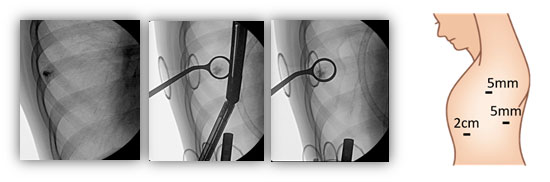

適応となる患者さんに対して、ヨード造影剤へのアレルギーがないことを確認します。手術当日、CT室へ移動してCTで確認しながら非常に細い針で微量の造影剤を腫瘍近傍に打ち込みます(下図1)。

次に、車いすで手術室に移動して手術を行います。手術中はレントゲンに写った造影剤をすべて切り取ることで腫瘍も一緒に切除されてきます(下図2)。そもそも、早期がんに対する部分切除を行うためには腫瘍の局在を確認する必要があります。これまでは直接触ることで腫瘍を確認していたため、傷が大きくなってしまいました。しかし、この方法では腫瘍を触る必要がありませんので、最小限の傷で手術を行うことができます。当科では2㎝の傷1つと5mmの傷2つを基本としています。